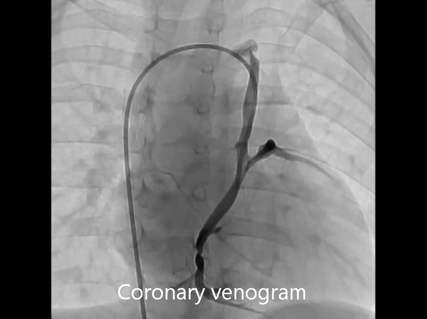

A 12 month-old male infant with known tricuspid and pulmonary atresia was admitted to our hospital for cardiac catheterization to evaluate his hemodynamic status prior to undergoing a bidirectional Glenn shunt (BDG) procedure. He was known to have undergone a left modified Blalock-Taussig shunt at 1 month of age, as well as an enlargement of an atrial septal defect using cardiopulmonary bypass at 4 months of age, and it was at this time that a coronary sinus orifice was intraoperatively identified. He had presented with dyspnea on exertion and cyanosis with systemic oxygen saturation of 85%. A chest X-ray showed a cardiothoracic ratio of 60% and a marginal decrease in the left pulmonary blood flow. Echocardiography showed that a left ventricular ejection fraction was 68% without significant valvular regurgitation. Electrocardiography showed the left axis deviation, right atrial hypertrophy and left ventricular hypertrophy without any ischemic change. Suprasternal echocardiography did not show any abnormal blood flow draining into the INV. Cardiac catheterization revealed that the pulmonary to systemic blood flow ratio, the mean pulmonary arterial pressure, the pulmonary arterial index, and cardiac index were 0.83, 9 mmHg, 154 cm2/m2, and 4.69 L/min/m2, respectively. However, a late phase left ventriculography image following angiographic evaluation of LSVC which was performed to investigate a veno-venous collateral showed retrograde blood flow through LSVC. Therefore, a 5Fr-left Judkins catheter was introduced from the femoral vein and advanced through the INV and the persistent LSVC into the coronary vein. A selective coronary venogram revealed that the coronary sinus ostium was absent and a retrograde coronary venous flow was observed through the persistent LSVC draining into the INV, i.e. a CSOA was identified (Fig. 1, Movie). When he was 19 months of age, we performed a BDG, repair of the coronary sinus orifice, and ligation of the LSVC. A re-median sternotomy was performed and after establishing cardiopulmonary bypass with bicaval cannulation, the left Blalock-Taussig shunt was ligated and divided. Following cardiac arrest using cold cardioplegia and a right atriotomy was performed, and a thin membrane was observed at the orifice of the coronary sinus (Fig. 2). We cut this membrane with enlargement of the orifice to adequately view the middle cardiac vein. Subsequently, the LSVC was ligated superiorly and divided, and after the right superior vena cava was divided, a bidirectional cavopulmonary shunt was performed. The patient was successfully weaned from the cardiopulmonary bypass and recovered uneventfully. A selective coronary angiography performed at 2 weeks after the BDG procedure showed adequate coronary venous flow draining into the right atrium. The patient was treated with oral administrations of asprin, diuretics and digoxin.

Movie Selective left coronary angiogram showing retrograde blood flow through the left superior vena cava.